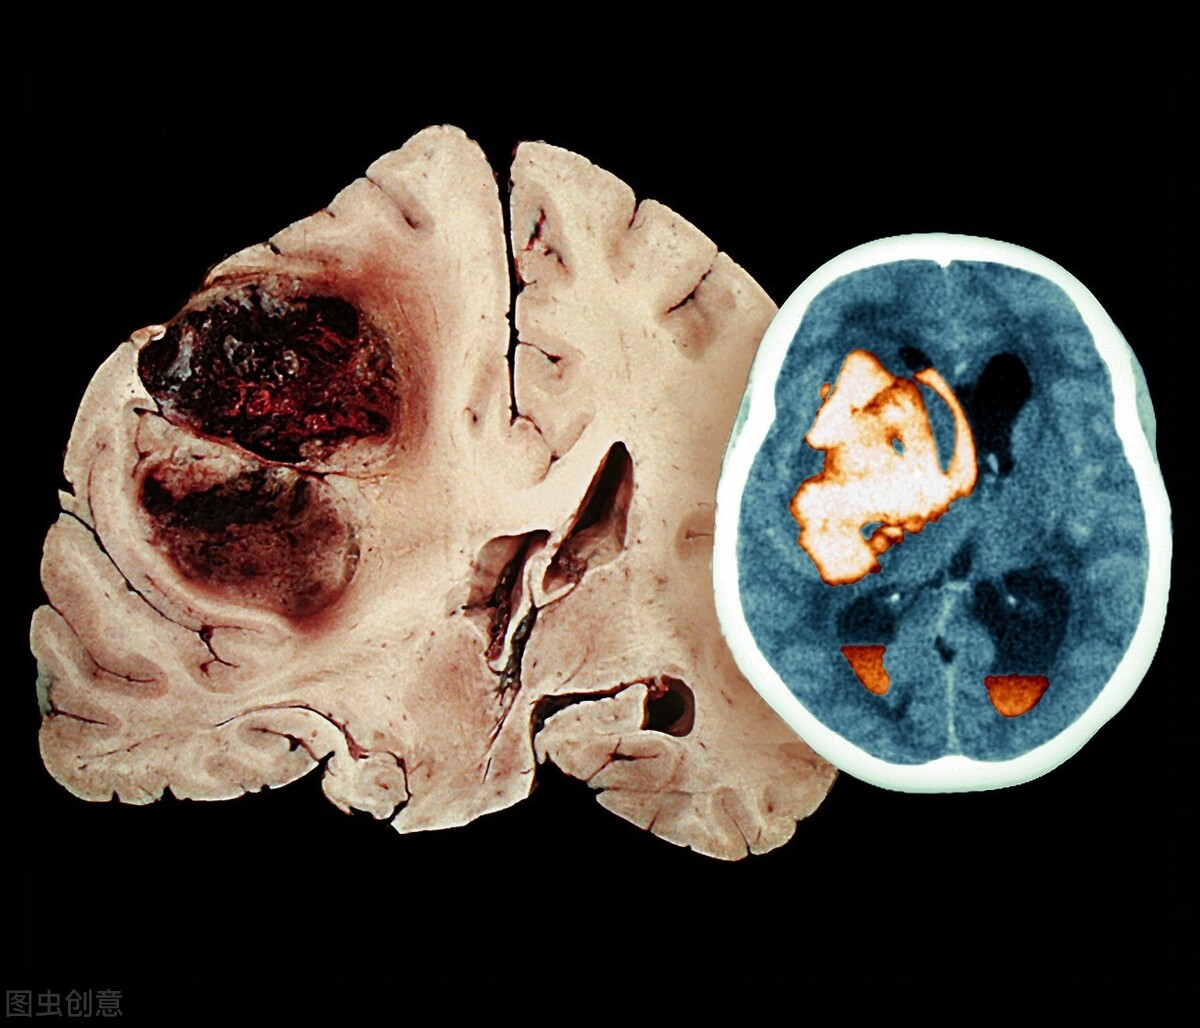

脑出血是脑卒中的一种,是指原发性非外伤性的脑实质出血,占急性脑血管病的20%-30%,具有高复发率、高致残率和高死亡率的特点。脑出血的症状包括头晕头痛、言语不清、口角歪斜、双眼视力障碍和一侧肢体麻木等。当发现周围人出现上述症状时,建议立即拨打120急救电话,将患者送往医院。及时就医可以降低患者的残疾率和死亡率。